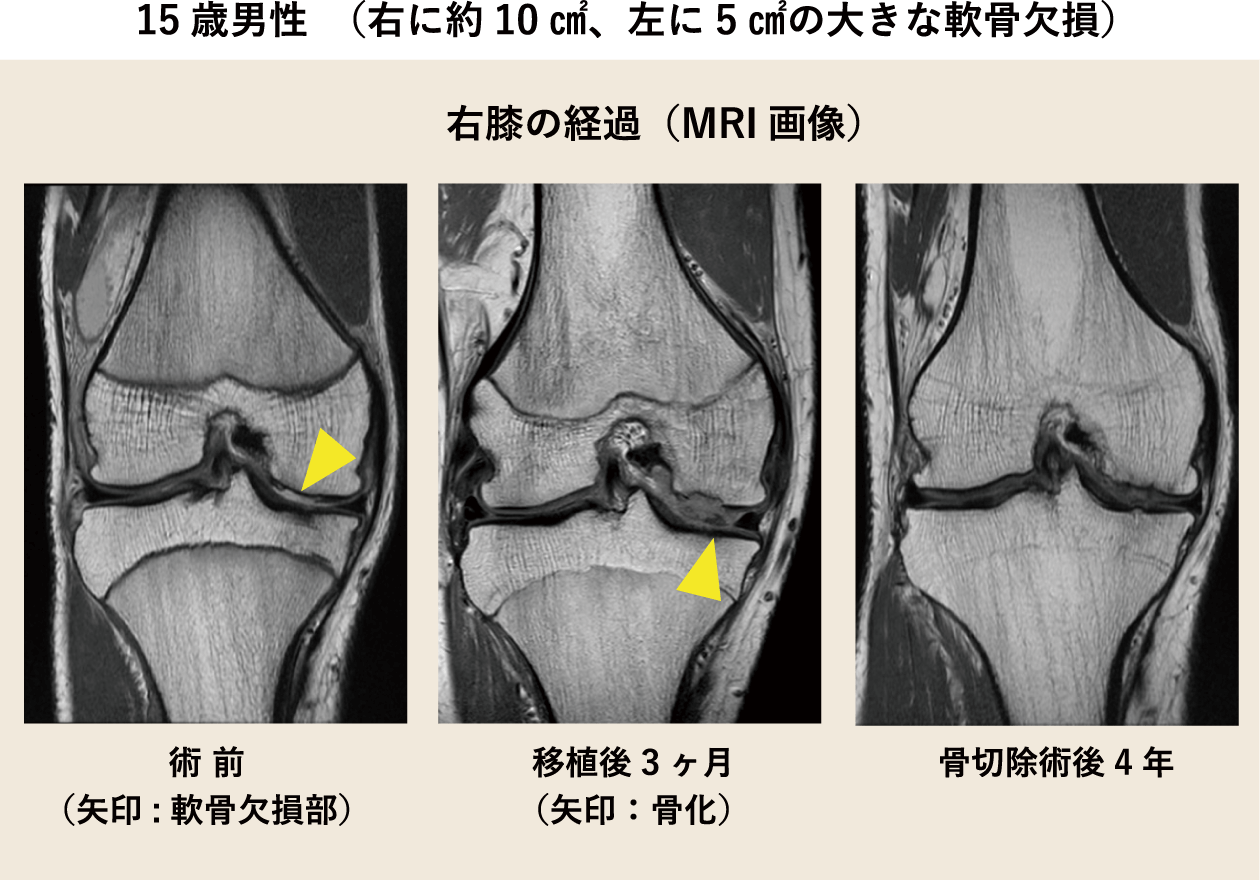

内尾:当科で治療し、処置が必要であった患者さんについてご紹介します。 15歳の男性でバスケットボールによるひざへの継続的な負担から、右に約10㎠、左に5㎠の大きな軟骨欠損がありました。 欠損が大きすぎて、従来の骨穿孔術や骨軟骨柱移植術だけでは対応できなかったため、 自家培養軟骨移植術と自家骨軟骨柱移植術を組み合わせて両ひざを治療することにしました。 当時、自家培養軟骨を欠損部に移植する際は、患者さんの脛から採取した骨膜で固定していました。 移植後、傷が治る過程でひざが腫れたり、可動域制限をしたりしていたのでひざの動きが一時的に悪くなりました。 また右膝の移植部が膨らみ、一部の軟骨が骨化しましたので、移植3ヶ月後に関節鏡視下で取り除くとともに関節の動きをよくしました。 その後、痛みはなくなり、患者さんの経過は良好です。 1年、2年と日が経つにつれ、スポーツも可能となり、生活の質(QOL)が改善しました。現在は6年が経過していますが順調です。

また、骨化の原因は骨膜であること、特に10代の患者さんに発生しやすいことがわかってきました。 現在は、骨膜ではなく人工のコラーゲン膜で固定するため、移植後の膨らみや骨化の心配はありません。 当科では10代の患者さんから60代の患者さんまで幅広く治療しています。患者さんのひざの状態に合わせて適切な治療を組み合わせています。